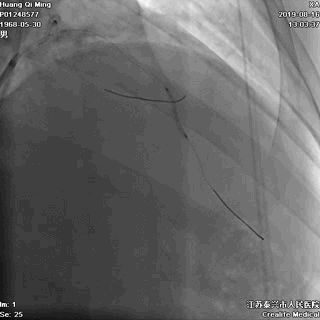

LCX PCI过程

手术器械:

7F EBU3.5

0.014” Runthrough NS

2.0*20 Maverick 球囊

2.75*23 DES

2.75*12 Quantum Maverick 球囊

3.0*8 Quantum Maverick 球囊

导丝通过病变

球囊扩张,PTCA

支架定位和植入

高压扩张使支架贴壁

LCX植入后即刻效果满意